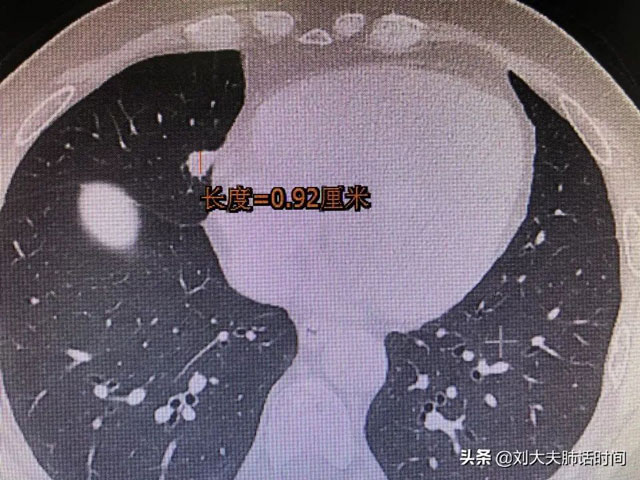

很多人只看结节的大小看到结节比较大或者有变大的趋势就觉得一定是肺癌,其实不然就比如下面两张报告

(报告1良性,报告2恶性)

肺结节中,95%都是良性结节,不需要做手术,只有5%是恶性结节(肺癌)。判断肺结节是良性还是恶性,先随访三个月比较肺结节的外部结构和内部特征非常重要。